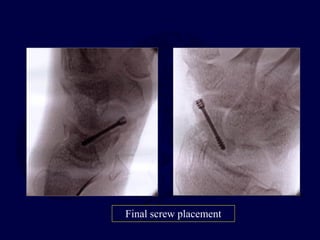

Trans-scaphoid Perilunate

Dislocations

Fix scaphoid first: dorsal

approach

Pin L-T and Mid-carpal

joints

Make sure

Radius-Lunate-

Capitate are

colinear and S-L

angle restored